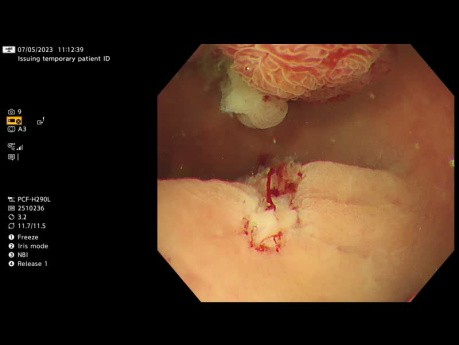

Resección mucosa endoscópica de tumor con extensión...

Video caso clínico: tumor con extensión lateral resecado en colon derecho. Las imágenes NBI no revelaron características endoscópicas preocupantes. El pólipo se eliminó con éxito mediante la técnica de...